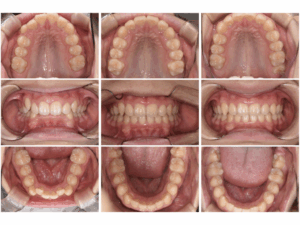

【 治療前 】 【 6ヶ月後 】 【 1.5 年後 】

〈 年齢・性別 〉 14 歳 男児

〈 主訴・相談内容 〉 下の歯をもっと見えるようにしたい

〈 診断名 〉 過蓋咬合

〈 装置 〉 Myobrace®︎ Medium stage1、stage2

〈 抜歯部位 〉 非抜歯

〈 治療期間 〉 1年で改善、その後経過観察(2年間)

〈 治療費 〉 280,000円 (税別・精密検査代別)※

〈 治療のリスク 〉 第2大臼歯の舌側傾斜、治療後の後戻り